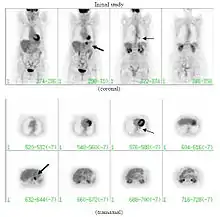

FDG-PET study of a 71-year-old woman with a solitary pulmonary nodule (thin arrow) in the left lower lobe near the heart. The scan also revealed abnormal increased activity at the gastro-esophageal junction (thick arrow). The final diagnosis was non-Hodgkin lymphoma at both sites.

If there is an intermediate risk of malignancy, further imaging with positron emission tomography (PET scan) is appropriate (if available). It can be done simultaneously as a CT scan in the form of PET-CT. Around 95% of patients with a malignant nodule will have an abnormal PET scan, while around 78% of patients with a benign nodule will look normal on PET (this is the test sensitivity and specificity).[15] Thus, an abnormal PET scan will reliably pick up cancer, but several other types of nodules (inflammatory or infectious, for example) will also show up on a PET scan. If the nodule has a diameter of less than one centimeter, PET scans are often avoided because of an increased risk of falsely normal results.[15][16][17] Cancerous lesions usually have a high metabolism on PET, as demonstrated by their high uptake of FDG (a radioactive sugar).